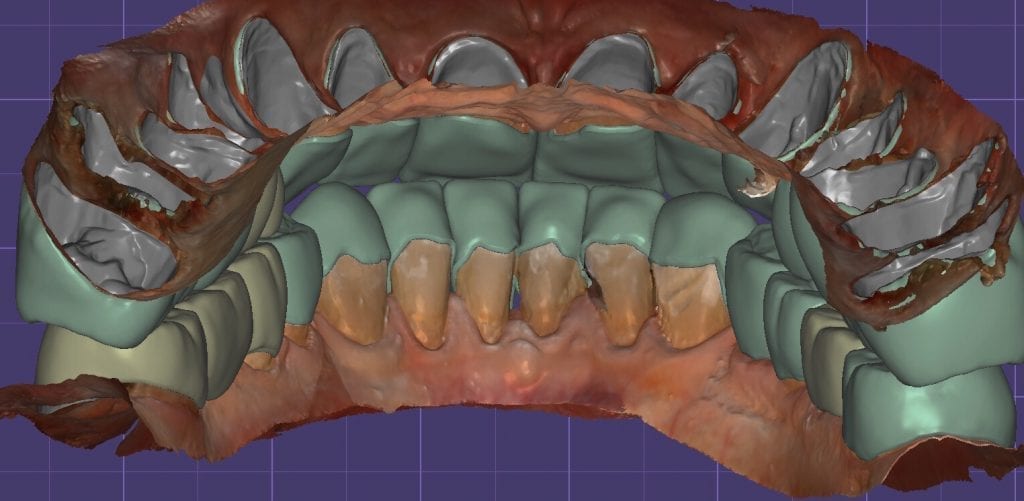

The digital models were then imported into a third party software where a library of tooth morphologies are available for the clinician to choose from.

Once the appropriate library is chosen, the digital wax ups are performed. In the subsequent photos you can see the transparent overlay of the wax-ups to the original position of the existing dentition